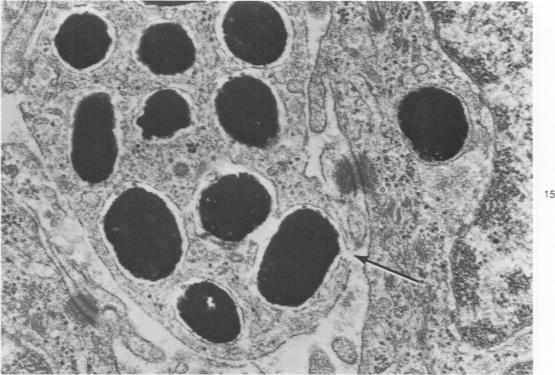

Melanin pigmentation of the corneal epithelium was induced in pigmented guinea pigs by the topical application of colchicine to their eyes or by corneal cauterization with silver nitrate. With colchicine the pigmentation was preceded by the development of an abnormal corneal epithelium in which numerous cells became arrested in cell division. The corneal melanosis resulted largely from the migration of melanocytes into the corneal epithelium from the normally pigmented contiguous conjunctiva and to a lesser extent from the presence of melanin granules within corneal epithelial cells. In both models a leukocytic and vascular invasion of the cornea proceded and accompanied the migration of melanocytes into the corneal epithelium. Electron microscopy disclosed cells with the same morphology as conjunctival melanocytes between the epithelial cells of the cornea. Mature melanin granules were also present within some squamous epithelial cells as individual granules or as clusters. The ultrastructural findings are viewed in relation to how melanin granules are transferred from melanocytes to epithelial cells. Evidence is presented which suggests that malanin granule transfer may follow the fusion of the membranes of the melanocytes and epithelial cells.

通过向有色豚鼠的眼睛局部应用秋水仙碱或用硝酸银进行角膜烧灼,可诱导角膜上皮的黑色素沉着。使用秋水仙碱时,色素沉着之前会出现异常的角膜上皮,其中许多细胞在细胞分裂中停滞。角膜黑变病主要是由于黑素细胞从正常色素沉着的相邻结膜迁移到角膜上皮,在较小程度上是由于角膜上皮细胞内存在黑色素颗粒。在这两种模型中,角膜均出现白细胞和血管浸润,并伴随黑素细胞迁移到角膜上皮。电子显微镜检查发现角膜上皮细胞之间存在与结膜黑素细胞形态相同的细胞。成熟的黑色素颗粒也以单个颗粒或簇的形式存在于一些鳞状上皮细胞内。结合黑色素颗粒如何从黑素细胞转移到上皮细胞来观察超微结构的发现。有证据表明,黑色素颗粒转移可能发生在黑素细胞和上皮细胞膜融合之后。